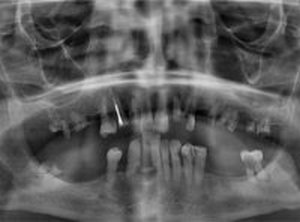

У моего знакомого 3 хороших зуба на верхней челюсти: 1 и 2 слева и 3 справа. Хочет протезировать, чтобы в зоне улыбки не торчало железо, никакое, даже кламмеры. Чтобы держалось и не отпадало.

При этом, железные, титановые коронки или кламмеры в зоне улыбки исключаются. Как и имплантаты, на которые цены не сложат.